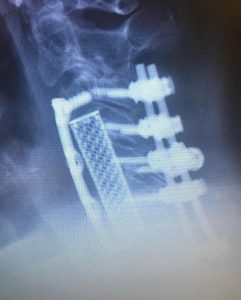

Here is an extreme example of a patient who came to me for correction of a previous attempt at surgery which failed to correct her severe Kyphosis and spinal cord compression. After the much more extensive surgery that I performed, she began to recover strength in her arms again and her ability to walk improved.